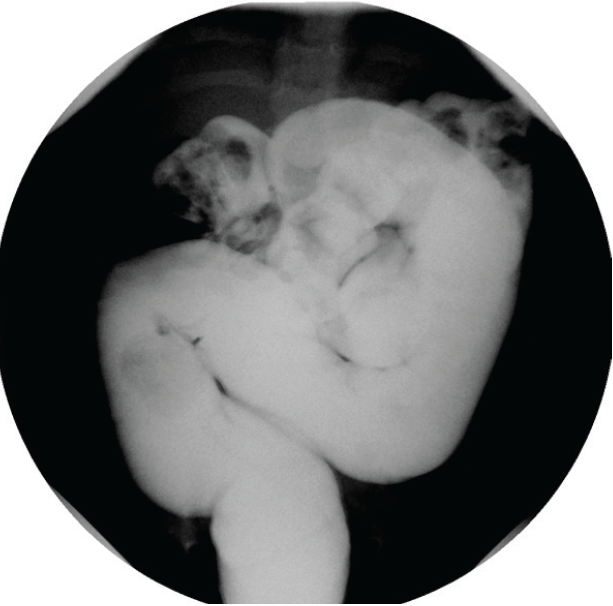

A 16-year-old boy presented to the emergency department with 2 weeks of worsening lower abdominal pain.

Salim Hommeida, MD; Michael Ishitani, MD; Imad Absah, MD

Constipation is a common gastrointestinal complaint among children, with an estimated worldwide prevalence of 0.7% to 29.6% in the pediatric population.